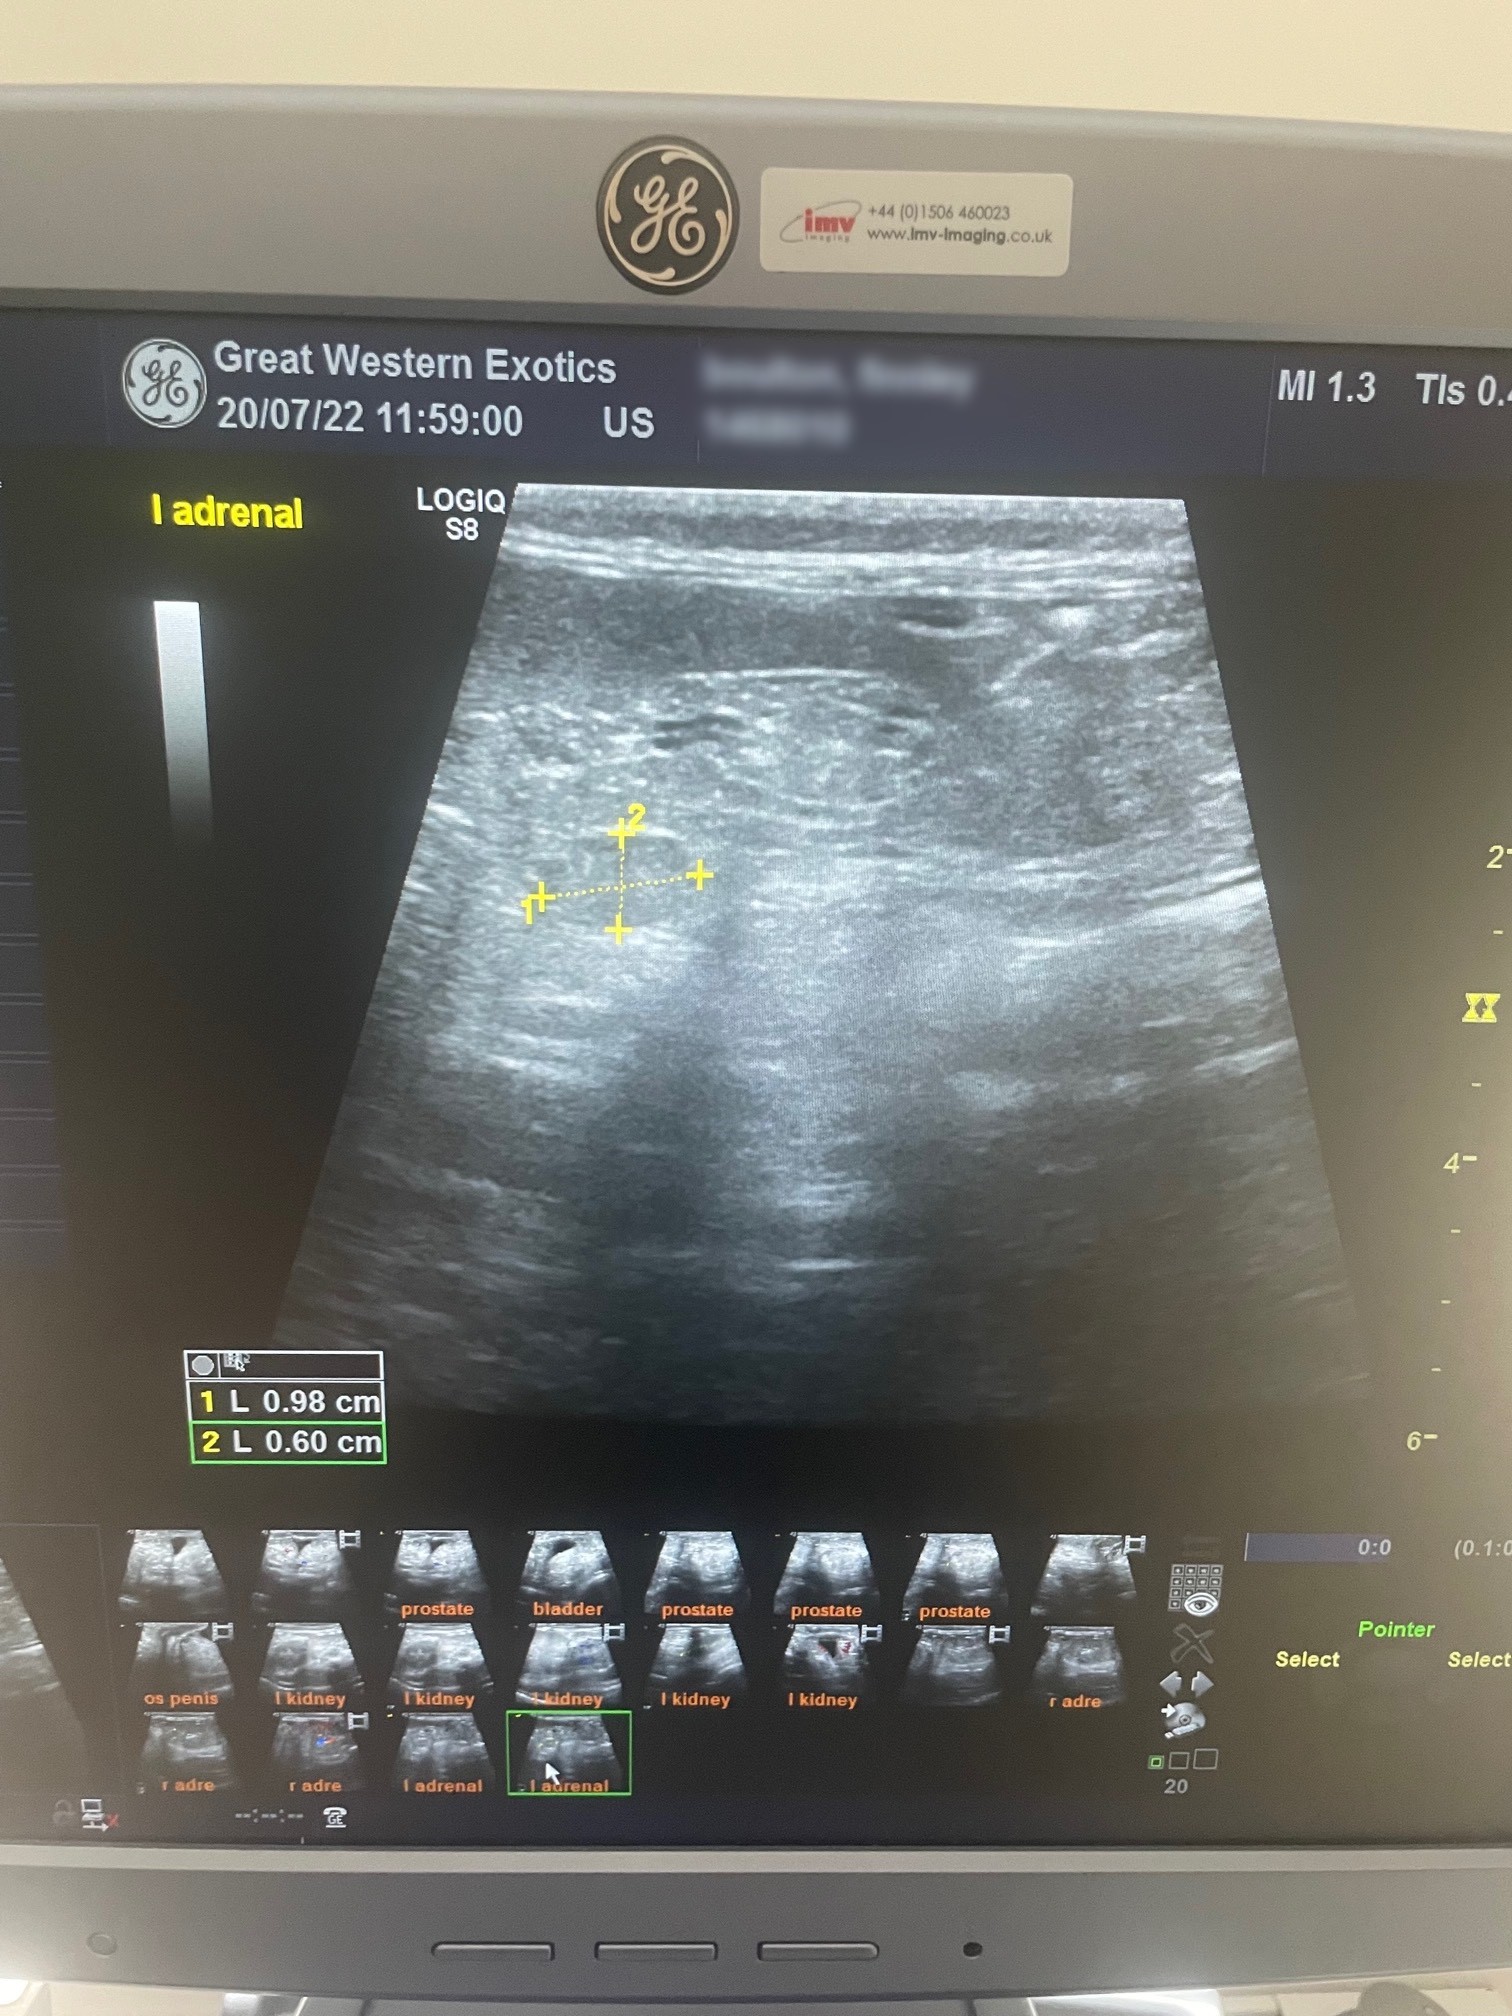

From exomcdmip.blob.core.windows.net

Normal Adrenal Gland Ultrasound at Robert Hoban blog Ferret Adrenal Gland Size this client education handout answers several questions for the ferret owner: The brain, the reproductive tract, and. adrenal gland disease (agd) in ferrets is one of the more common conditions that affects ferrets in north america. What is an adrenal gland? adrenal gland disease in ferrets is unique to this species, with clinical signs and pathophysiology different.. Ferret Adrenal Gland Size.